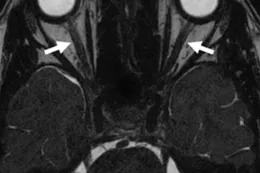

A Steady-state free precession (SSFP) axial image showing the optic nerves (arrows).

Optic canal (asterisks) and superior orbital fissure (arrow)